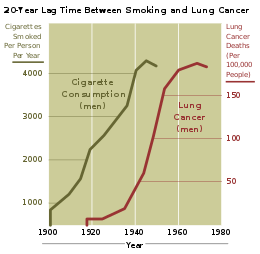

Smoking

Smoking, particularly of cigarettes, is by far the main contributor to lung cancer.[22] Cigarette smoke contains at least 73 known carcinogens,[23] including benzo[a]pyrene,[24] NNK, 1,3-butadiene and a radioactive isotope of polonium, polonium-210.[23] Across the developed world, 90% of lung cancer deaths in men during the year 2000 were attributed to smoking (70% for women).[25] Smoking accounts for about 85% of lung cancer cases.[1]

The population segment most likely to develop lung cancer is people aged over 50 who have a history of smoking. In contrast to the mortality rate in men, which began declining more than 20 years ago, women's lung cancer mortality rates have been rising over the last decades, and are just recently beginning to stabilize.[143] In the USA, the lifetime risk of developing lung cancer is 8% in men and 6% in women.[6]

For every 3–4 million cigarettes smoked, one lung cancer death occurs.[144] The influence of "Big Tobacco" plays a significant role in the smoking culture.[145] Young nonsmokers who see tobacco advertisements are more likely to take up smoking.[146] The role of passive smoking is increasingly being recognized as a risk factor for lung cancer,[31] leading to policy interventions to decrease undesired exposure of nonsmokers to others' tobacco smoke.[147]

History

Lung cancer was uncommon before the advent of cigarette smoking; it was not even recognized as a distinct disease until 1761.[157] Different aspects of lung cancer were described further in 1810.[158] Malignant lung tumors made up only 1% of all cancers seen at autopsy in 1878, but had risen to 10–15% by the early 1900s.[159] Case reports in the medical literature numbered only 374 worldwide in 1912,[160] but a review of autopsies showed the incidence of lung cancer had increased from 0.3% in 1852 to 5.66% in 1952.[161] In Germany in 1929, physician Fritz Lickint recognized the link between smoking and lung cancer,[159] which led to an aggressive antismoking campaign.[162] The British Doctors' Study, published in the 1950s, was the first solid epidemiological evidence of the link between lung cancer and smoking.[163] As a result, in 1964 the Surgeon General of the United States recommended smokers should stop smoking.[164]